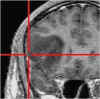

Cavernoma

profondo

Glioblastoma

in area critica

Il procedimento ha inizio con l’esecuzione di una Risonanza Magnetica (RM) o di una Tomografia Computerizzata (TC) del paziente, effettuate mediante protocolli di acquisizione dedicati.

Al momento dell’intervento chirurgico, il capo del paziente viene registrato nello spazio tridimensionale del computer tramite un sistema di localizzazione, generalmente ottico a infrarossi, che riconosce specifici punti di repere applicati al capo o al sistema di fissaggio.

Il computer provvede quindi a sovrapporre l’anatomia reale del paziente alle immagini RM o TC precedentemente acquisite. Durante l’intervento, il chirurgo utilizza strumenti chirurgici dotati di marker che vengono continuamente rilevati dallo stesso sistema ottico a infrarossi; in questo modo il neuronavigatore è in grado di indicare in tempo reale, sulle immagini RM o TC, l’esatta posizione degli strumenti all’interno del campo operatorio.

Grazie a questa tecnologia, l’intervento viene accuratamente pianificato alla consolle del computer, anche nei giorni precedenti l’atto chirurgico, consentendo di valutare in modo approfondito il percorso di accesso più sicuro e riducendo significativamente il rischio di dover effettuare scelte intraoperatorie non sufficientemente ponderate.

Per raggiungere una determinata sede, anche se profonda o localizzata in aree critiche, è possibile adottare traiettorie talvolta più lunghe ma che attraversano regioni cerebrali a minore rischio funzionale per il paziente. In questo modo sono venuti meno molti dei limiti legati alla difficoltà di accesso anatomico (lesioni profonde, sedi eloquenti), che in passato spesso precludevano un trattamento chirurgico.